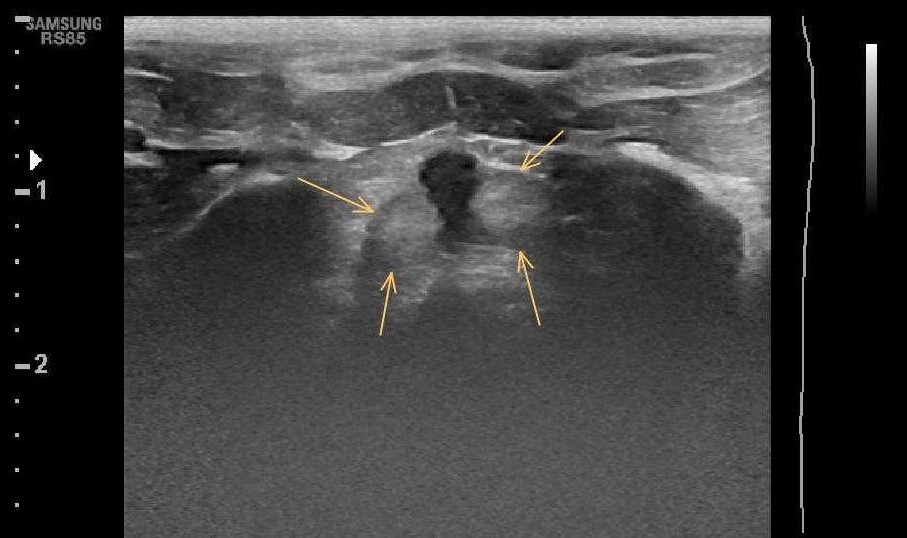

Onemocnění prostaty se u kocourů na rozdíl od psů nevyskytují často. Nejčastěji jsou popisovány neoplazie prostaty, konkrétně karcinom a adenokarcinom. Jedná se většinou o agresivní tumory s vysokým metastatickým potenciálem. Kromě nádorů prostaty jsou zmiňovány i prostatitidy nebo paraprostatické cysty. Bez ohledu na příčinu vykazují postižení kocouři příznaky onemocnění dolních cest močových (dysurie, polakisurie, hematurie, inkontinence), dyschezii nebo obstipaci. V pokročilých fázích onemocnění se mohou vyskytovat i nespecifické systémové příznaky (apatie, inapetence, hubnutí, dyspnoe). Zásadní roli v diagnostice hrají zobrazovací metody a následně patomorfologické vyšetření. I když se z hlediska četnosti nejedná o častý problém, v diferenciální diagnostice kocourů s výše popsanými klinickými příznaky bychom prostatopatie neměli vynechávat.

Prostate diseases are not very common in male cats, unlike in dogs. The most commonly reported are prostate tumors, specifically carcinoma and adenocarcinoma. These are mostly aggressive tumors with high metastatic potential. In addition to prostate cancer, prostatitis and paraprostatic cysts are also mentioned. Regardless of the cause, affected cats show symptoms of lower urinary tract disease (dysuria, pollakiuria, hematuria, incontinence), dyschezia, or constipation. In advanced stages of the disease, nonspecific systemic symptoms (lethargy, loss of appetite, weight loss, dyspnea) may also occur. Imaging methods and subsequent pathomorphological examination play a key role in diagnosis. Although it is not a common problem in terms of frequency, prostatopathy should not be overlooked in the differential diagnosis of male cats with the clinical symptoms described above.*